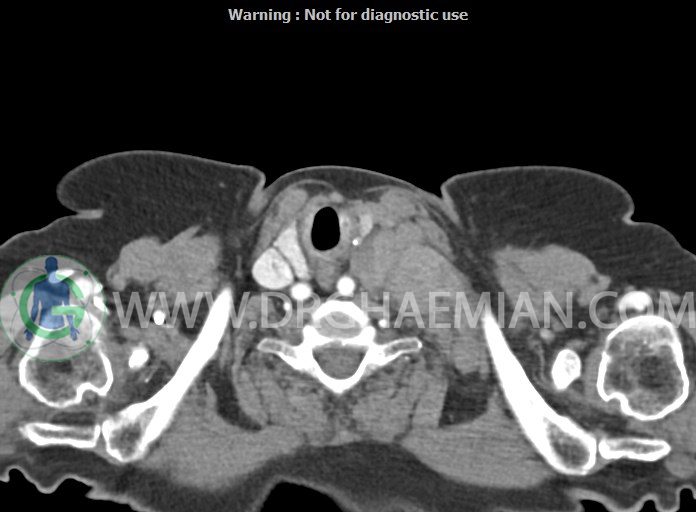

در سی تی اسکن اسپیرال از گردن با تزریق (مولتی دیدکتور 16 با مقاطع ظریف و بازسازی های ساژیتال و کرونال):

– تصویر توه های نسج نرمی oval shape متعدد با Enhancement تقریباً هوموژن، قرار گرفته در سمت چپ گردن، در لول غضروف کریکوئید با اثر فشاری شدید و compression ورید ژوگولار، با گسترش تحتانی به اینفراکلاویکولار چپ، به حداکثر ابعاد 28x50mm (با Enhancement مختصر هتروژن در این توده)

در درجه اول مطرح کننده لنفادنوپاتی متاستاتیک مطرح می باشد بالین، تومورهای منشأ گرفته از غلاف عصبی زنحیره سمپاتیک چپ گردنی، شبکه براکیال و لنفوم نیز در DDX قرار دارند. لذا نمونه برداری بافتی جهت بررسی بیشتر توصیه می شود.

– اسکولیوز مهره های سرویکال با تحدب به راست، احتمالاً در زمینه اثر فشاری توده های مذکور

مشهود است.